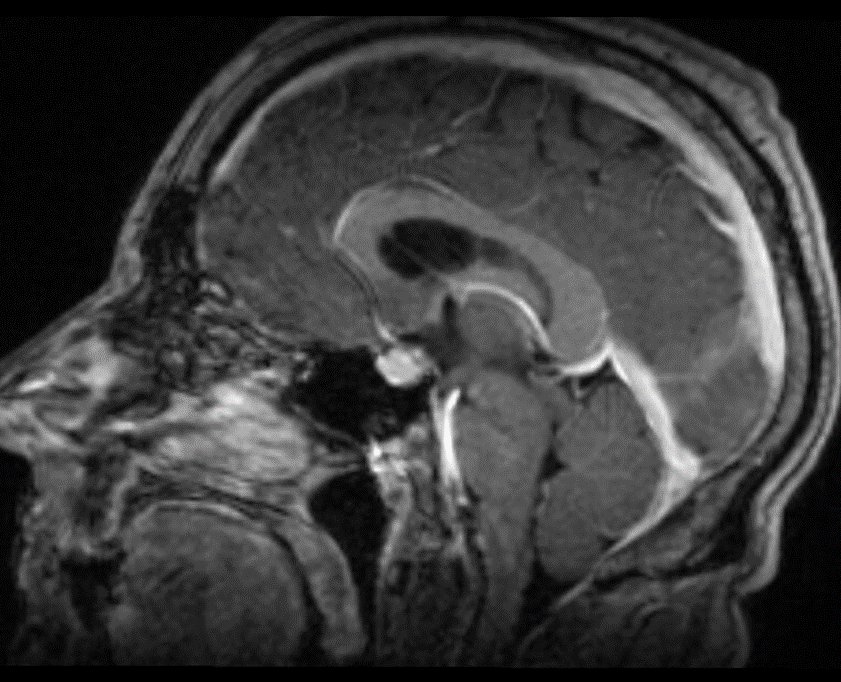

Excited to announce that application for our Skull Base and Pituitary Surgery Fellowship is now open.